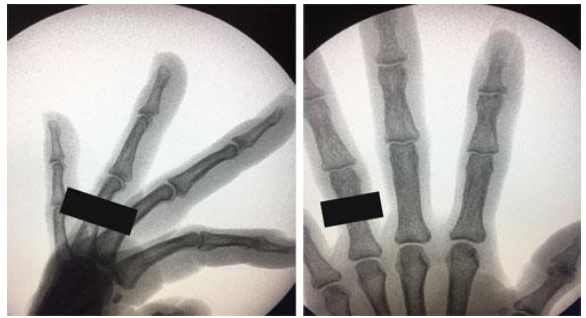

A 35-year-old man comes to the office because of a painless enlargement of the right index finger for the past 6 months. An x-ray study is shown. Curettage of the lesion and grafting with demineralized bone matrix are planned. Which of the following is the most likely outcome of this procedure in this patient?

The correct response is Option E.

Uneventful healing without recurrence is most likely in this patient. The bone lesion pictured in the x-ray is characteristic of an enchondroma. Enchondromas are benign chondrogenic tumors arising from aberrant cartilaginous foci within the medullary canal. Chondroblasts are thought to escape from the physis and proliferate in the metaphysis.

Enchondromas are the most common bone tumor found in the hand (approximately 90%). They are found mostly in the proximal phalanx, middle phalanx, and metacarpal. Enchondromas are benign, expansile, and locally destructive lesions. They are usually asymptomatic and discovered incidentally on radiographs taken for another reason. Pain is more frequently associated with a malignant tumor such as a chondrosarcoma or a pathologic fracture from cortical thinning. Typical radiographic features are a well-circumscribed, radiolucent lesion that may be expansile or purely lytic with popcorn stippled calcification.

Smaller asymptomatic lesions can be observed. Larger lesions that are potentially unstable or symptomatic are treated by curettage with or without bone grafting. Many authors recommend the addition of autologous or allograft bone following tumor excision. However, there are studies showing no benefit to adding bone graft or bone graft substitute. There is no consensus on the treatment of lesions involving a pathologic fracture. Stable fractures should be treated with immobilization and allowed to heal prior to treating the enchondroma secondarily. Unstable fractures can be safely treated with curettage and fracture fixation in a single stage.

Enchondromas are benign and complete resection is curative. Recurrence of a lesion after surgery may suggest that the lesion is actually a low-grade sarcoma. The risk of malignant transformation in a solitary enchondroma is approximately 1%.

Pathologic fractures are relatively common, especially in the hand. These occur with minor trauma when the lesion has resulted in significant cortical thinning but expansion of the tumor into the surrounding soft tissue does not occur.

The potential for malignant transformation is greatly increased in multiple enchondromatosis, such as Ollier disease and Mafucci syndrome. Ollier disease is a nonhereditary form of multiple enchondromatosis associated with skeletal dysplasia. Mafucci syndrome is characterized by multiple enchondromatosis and cutaneous hemangiomas. The risk of malignant transformation to chondrosarcoma or osteosarcoma in these cases is up to 30%. Low-grade chondrosarcomas have a low metastatic potential.